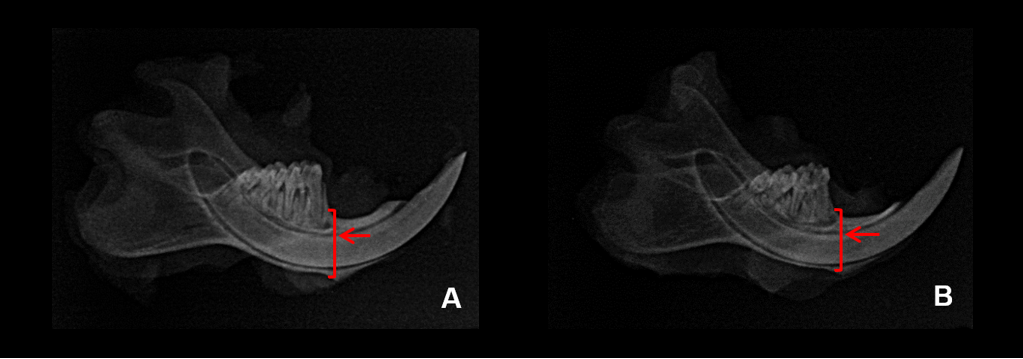

Thickness of the left hemi-mandibles

The mandibular thickness (Table 3) of the HFD group was significantly lower (p<0.05) when compared to the CD group. Some of the images obtained through digital radiography can be seen in Figure 3.

Fig. 3 - Radiographs of rat mandibles. A: CD group B: HFD group. Arrows indicate mandibular thickness